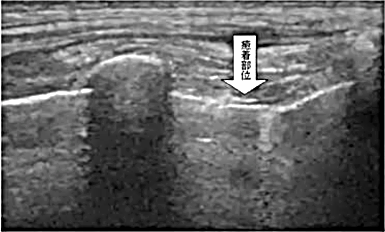

生体胸部の超音波画像撮影方法及び生体胸部の癒着診断方法